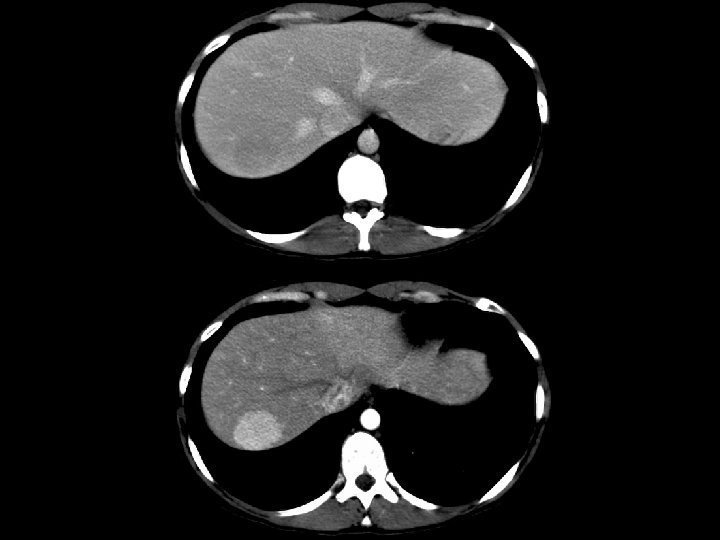

Lymphoma • Findings: – Innumerable low density lesions of the liver and one in the spleen • ddx: – Metastatic disease – Fungal abscesses